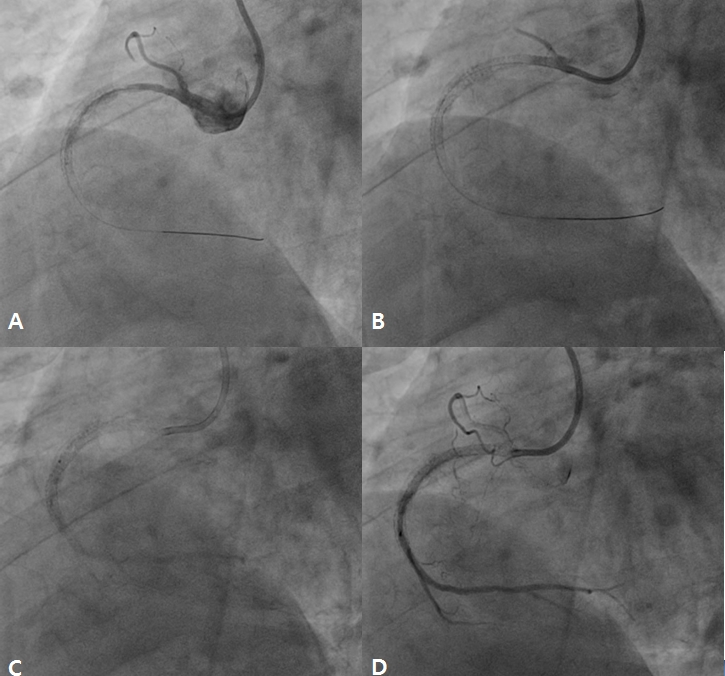

A 78 year-old male visited the outpatient department of Chonnam National University Hospital with intermittent chest pain for 4 months. He underwent percutaneous coronary intervention (PCI) for acute myocardial infarction (AMI) using bare metal stent in the proximal right coronary artery (RCA) 8 years ago. After that, he had undergone repeat intervention using drug eluting ballooning 7 years ago and PCI for mid RCA 6 years ago due to repeated in-stent restenosis (ISR) in RCA. He was treated with dual anti-platelet therapy of aspirin (100 mg daily) and clopidogrel (75 mg daily). Recently, he suffered from chest pain intermittently and was taken to our hospital. The 12-lead electrocardiogram showed normal sinus rhythm and left bundle branch block (no interval change) (Figure 1), and the level of cardiac enzymes were within normal range. He underwent elective coronary angiography (CAG), and it revealed chronic total occlusion in proximal RCA (Type IV ISR) (Figure 2A) with moderate stenosis in proximal left descending artery (LAD). We considered to do staged PCI for proximal LAD. After wiring into RCA with microcatheter backup, stepwise ballooning using 1.5 mm and 2.5 mm diameter balloon was done. Then, a 3.5 x 38 mm everolimus-eluting stent (Xience Alpine®) was implanted at proximal RCA (Figure 2B). Just after stenting with up to 10 atmospheres, no reflow below the lesion site was shown on follow-up CAG (Figure 2C). Coronary blood flow was not restored after intracoronary adenosine, nicorandil and glycoprotein IIb/IIIa inhibitor bolus injection in RCA (Figure 2D). Although we did additional ballooning from distal to proximal RCA again and again (Figure 3A), follow-up CAG showed still no reflow in RCA (Figure 3B). So, we infused intracoronary adenosine and nicoradil using microcatheter from proximal to distal RCA selectively (Figure 3C). Final CAG showed improved antegrade flow (TIMI III) in RCA without significant residual stenosis (Figure 3D). He was transferred to coronary care unit and monitored with anticoagulation for 1 day.

Figure 3. After additional ballooning from distal to proximal right coronary artery (RCA) (A), there was still no-reflow in RCA (B). Intracoronary adenosine and nicorandil was selectively infused using microcatheter from distal to proximal RCA (C). Final coronary angiography showed improved antegrade flow in RCA without significant residual stenosis (D).